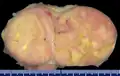

Gross pathology of an atypical solitary fibrous tumor, evidenced by some deeply yellow necrotic areas -